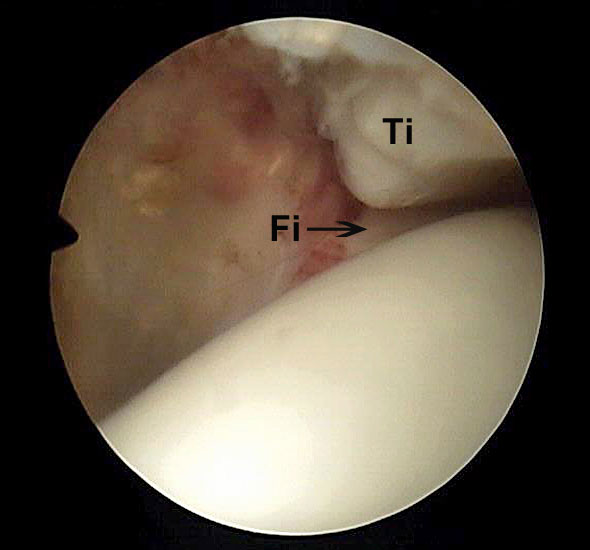

Abbildung 6 und 7, Video 2

Typischer Befund eines fibrotischen Faszikels (*), das zu einem Impingement am rechten lateralen Talus führt. Nach der Resektion des Faszikels ist der Blick auf das anterolaterale Gelenkeck zwischen der Tibia (Ti) und der Fibula (Fi) möglich.

Bei der intraoperativen Palpation mit dem Tasthaken zeigt sich die straffe Spannung des Faszikels und das mechanische Impingement an der lateralen Talusschulter. Oftmals finden sind entzündlich veränderte Synoviaanteile am Faszikel oder auch Schliffspuren am Knorpel der Taluskante.